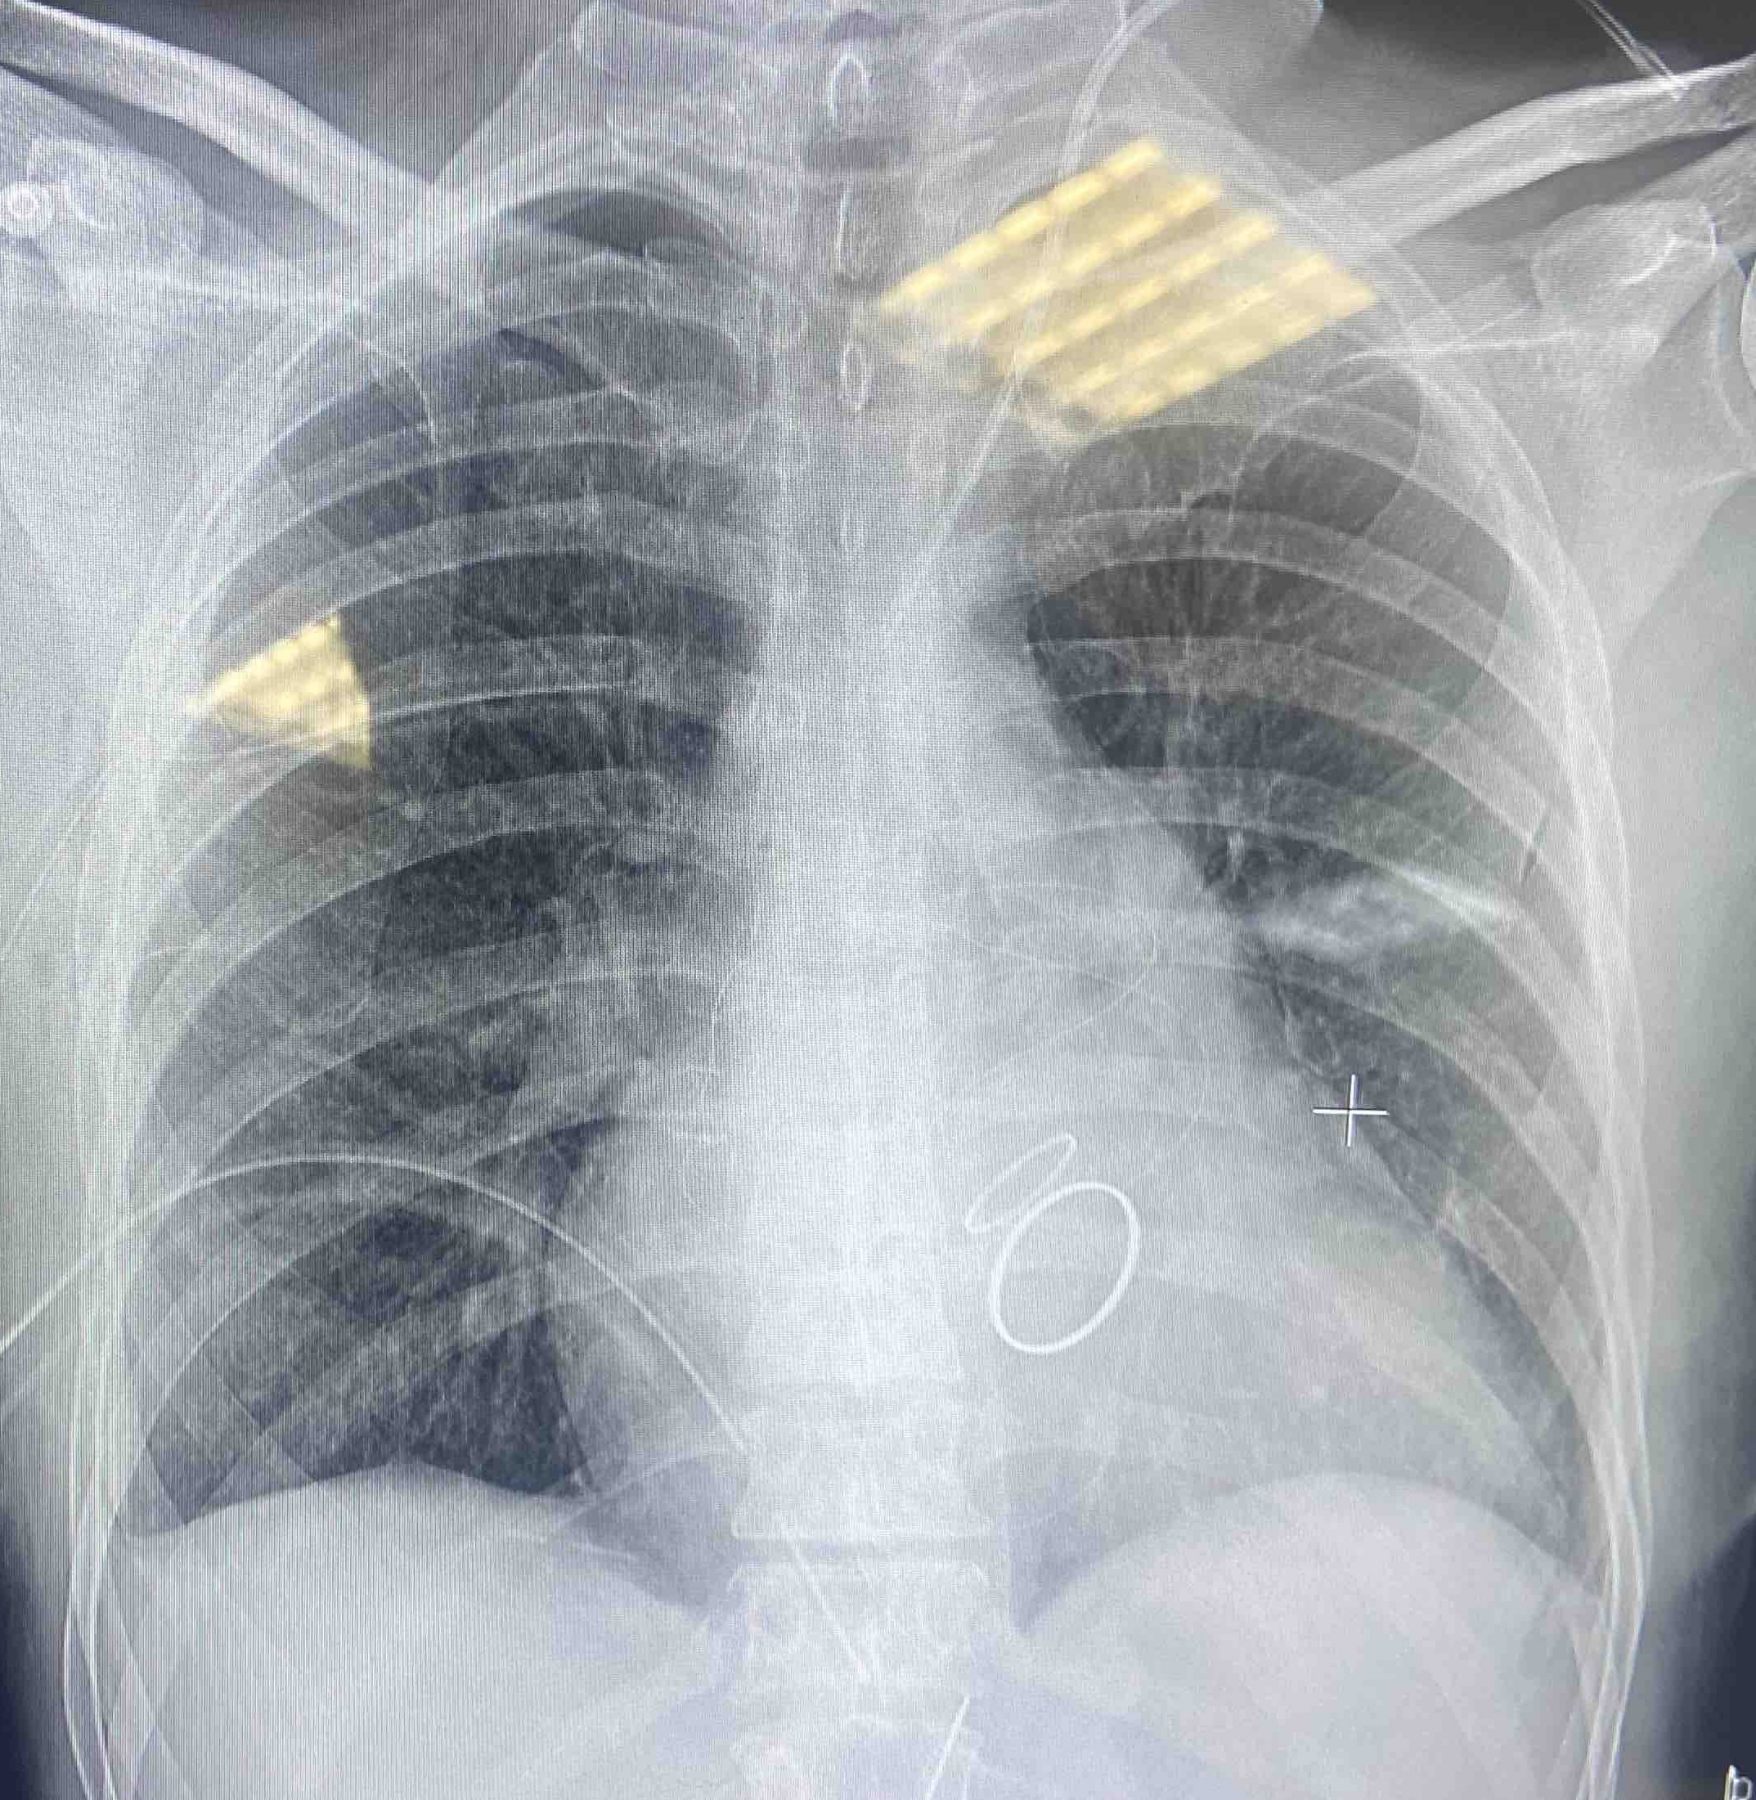

Pacienta a fost o femeie de 42 de ani ce suferea de o afecțiune reumatică. Boala i-a afectat ambele valve cardiace, prin îngustarea lor (Stenoza valvulară), încât fluxul de sânge circula cu dificultate în inimă. Unica soluție de a trata afecțiunea a fost tratamentul chirurgical.

”A fost realizată o intervenție cardiacă minim-invazivă complexă pentru înlocuirea ambelor valve (mitrală, aortică), având o durată de 5 ore. Evoluția după operație fiind una favorabilă, cu extubarea pacientei la 2 ore postoperator. Recuperarea cardiacă și externarea la domiciliu s-a reușit într-un timp redus. ” spune chirurgul operator Ghenadie Bostan.